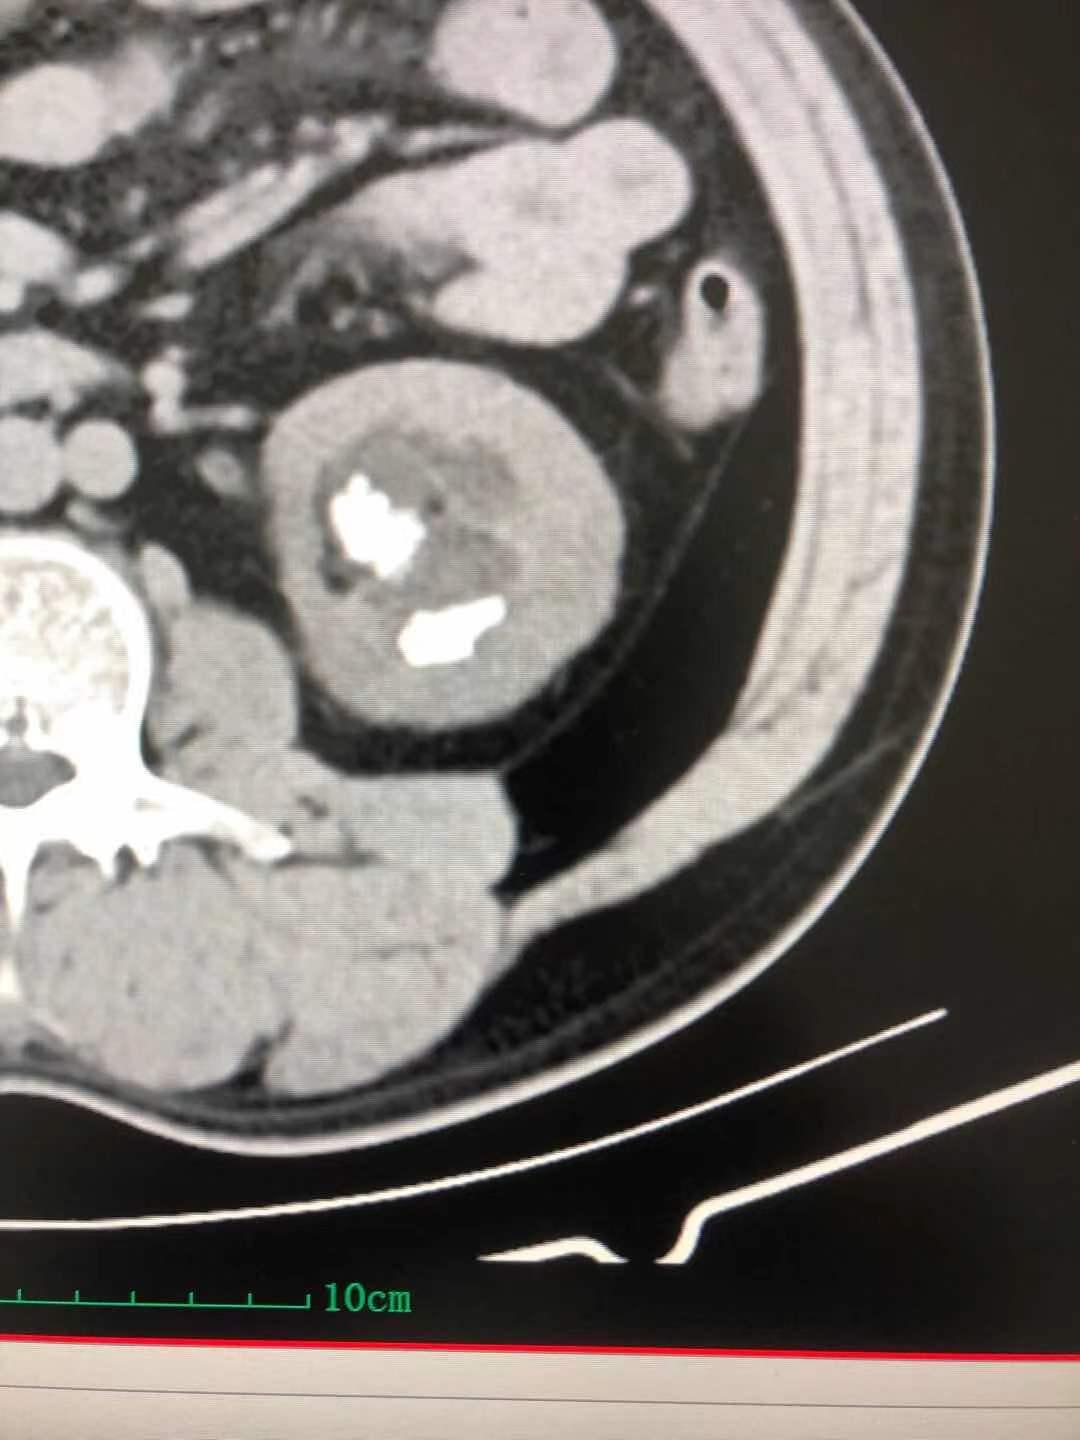

患者,男,40岁,以“间断性左侧腰腹部酸疼不适1月半”,入住我院泌尿外科。患者1月半前无明显诱因,出现左侧腰腹部间断性轻度酸疼不适,无恶心反胃,无寒战、发热,无咳嗽、咳痰,无尿频、尿急、尿痛,无肉眼血尿,3天前在利辛县某医院查腹部CT显示:左肾多发结石伴肾积水,最大结石约31mmX18mm,其就诊医生告诉患者其结石较大,需到省级以上医院就诊。患者经多方打听到我院可以治疗较大肾结石,遂来我院就诊。门诊医师以“左肾结石”收住入院。

入院后泌尿外科张国田主任仔细阅读患者泌尿系CT,诊断患者为左肾铸形结石合并肾盏结石,经过科室讨论,决定行“经皮肾镜左肾结石碎石取石术”。

积极术前准备,由手术室配合在全麻下行“经皮肾镜左肾结石碎石取石术”,手术历时约一个小时完成,不仅击碎并取净了肾盂内的铸形结石,连肾盏内的结石也一并击碎取出,术后患者恢复良好,于1周后出院,为表示感谢,特地送来一面锦旗。